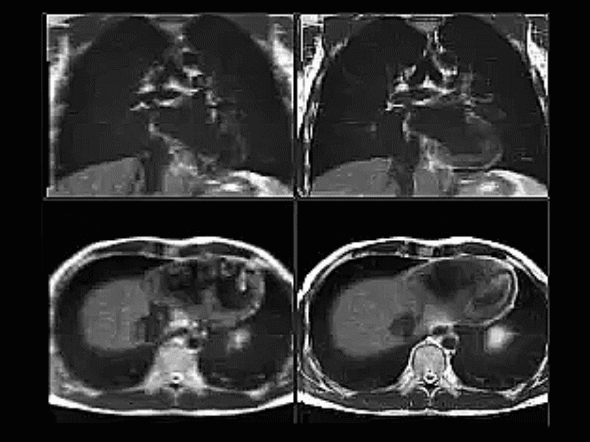

Physicists from The Institute of Cancer Research, London, and our partner hospital, The Royal Marsden NHS Foundation Trust, combined standard 2D magnetic resonance imaging (MRI) images of the chests of healthy volunteers to create 'super-resolution' videos, showing the lungs expanding and contracting.

The technique creates images of structures inside the body that are five times more detailed than other methods using MRI, and can also be carried out more quickly.

The technique developed by ICR researchers also reproduces detailed images of 'slices' of the body, at any position or time, by combining multiple MRIs of the body from different orientations.

The high definition images also have fewer 'artefacts' than standard MRI images – visible glitches caused by missing data that can obscure important structures in the body, compared with other similar techniques.